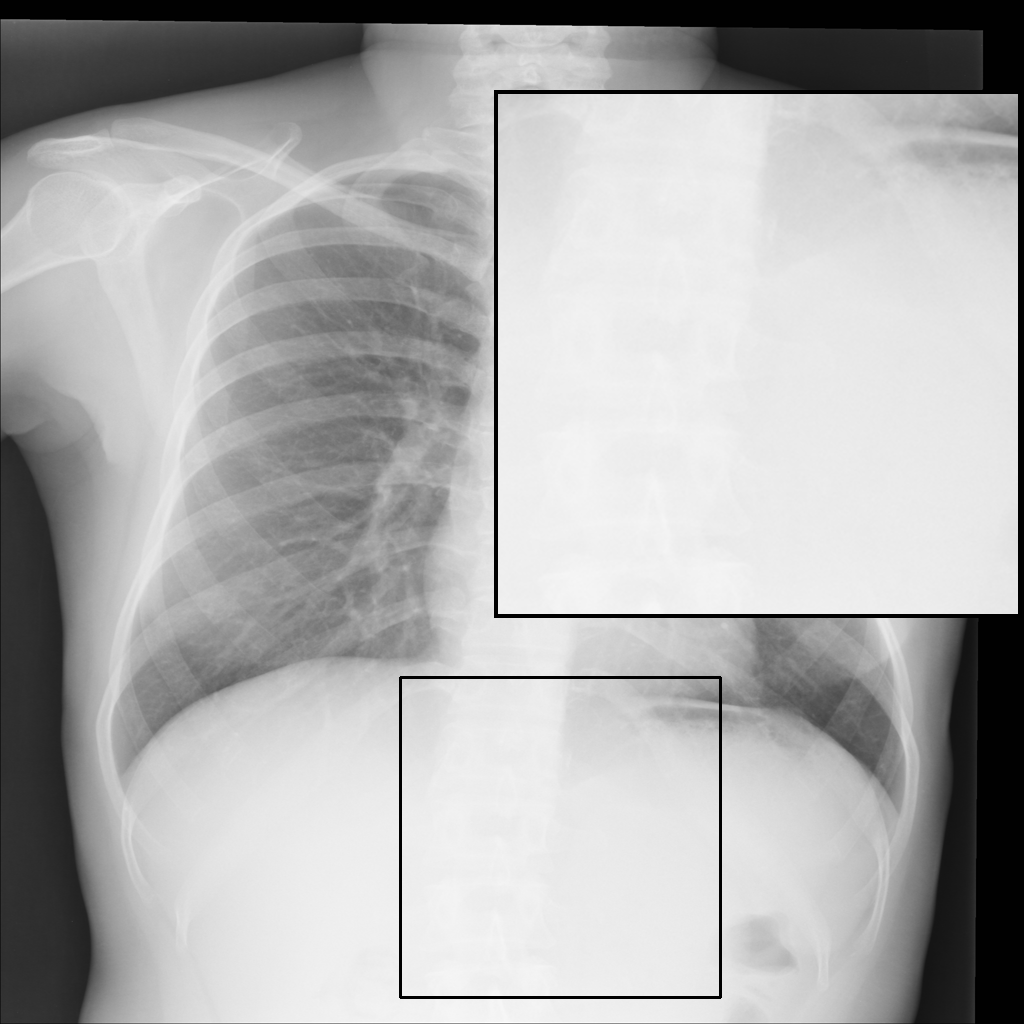

Fig. 3 shows image samples from the above datasets.

Figure 3: Image diversity across four datasets: (a) JSRT, (b) Montgomery County X-ray, (c) NIH ChestX-ray14, and (d) CheXpert

We developed a patch-wise U-Net-based architecture that processes two 512×512512\times 512-pixel regions of interest (ROIs) for each image; one centered on the upper spinal cord and another on the lower spinal cord. As shown in Fig. 3, our datasets exhibit diverse spatial characteristics, with images varying in dimensions (e.g., 2048×20482048\times 2048, 4020×48924020\times 4892, and 1024×10241024\times 1024 pixels) and bit depths (8-bit and 12-bit). This variability in image features poses a significant challenge for creating a robust enhancement model.